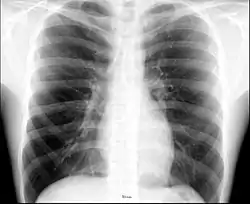

The human thorax includes the thoracic cavity and the thoracic wall. It contains organs including the heart, lungs, and thymus gland, as well as muscles and various other internal structures. Many diseases may affect the chest, and one of the most common symptoms is chest pain.

Different types of diseases or conditions that affect the chest include pleurisy, flail chest, atelectasis, and the most common condition, chest pain. These conditions can be hereditary or caused by birth defects or trauma. Any condition that lowers the ability to either breathe deeply or to cough is considered a chest disease or condition.

The major pathophysiologies encountered in blunt chest trauma involve derangements in the flow of air, blood, or both in combination. Sepsis due to leakage of alimentary tract contents, as in esophageal perforations, also must be considered. Blunt trauma commonly results in chest wall injuries (e.g., rib fractures). The pain associated with these injuries can make breathing difficult, and this may compromise ventilation. Direct lung injuries, such as pulmonary contusions (see the image below), are frequently associated with major chest trauma and may impair ventilation by a similar mechanism.